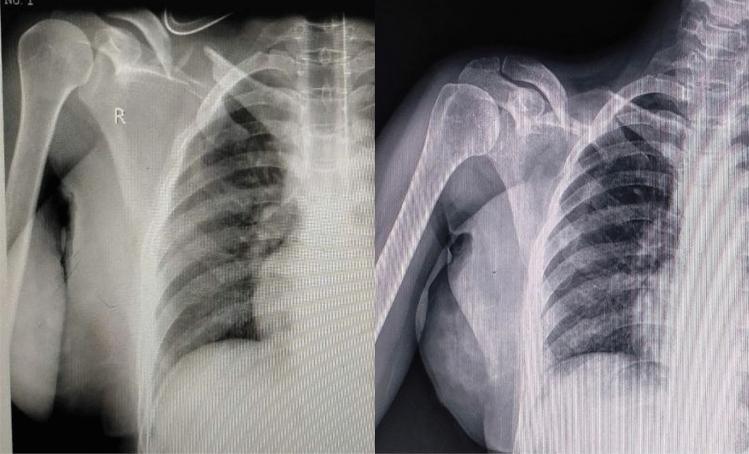

宽臂吊带与8字绷带:印度人群中锁骨中段骨折保守治疗的更佳选择

Broad Arm Sling vs Figure of 8 Bandage: The Better Choice in Conservative Management of Middle Third Clavicle Fractures in Indian Population.

A prospective randomised trial was conducted to compare the results of conservative management of middle-third clavicular fracture using the figure of 8 bandage and broad-arm sling.

METHODS

296 patients with middle-third clavicle fracture were included in the study conducted between March 2017 and January 2020. 152 patients were managed with figure of 8 bandage and 144 patients were managed with a broad arm sling. Results were evaluated based on clinical, radiological and functional outcomes. Visual analogue scale (VAS) for pain was used to evaluate the clinical outcomes, whereas radiological outcomes were assessed with non-union, malunion, clavicle shortening and time to union. Disability of Arm, Shoulder and Hand score (DASH), Constant score and Nottingham Clavicle Score were used to assess functional outcomes.

RESULTS

The broad arm sling group showed a significantly better VAS score in the first 4 weeks. DASH score was significantly superior in the broad arm sling group in the initial 4 weeks, but with similar outcome thereafter. Constant scores showed a good outcome for both groups at the final follow-up, whereas the Nottingham Clavicle Score was significantly superior in the broad arm sling group at the 2 year follow-up. A satisfactory outcome was achieved with respect to the radiological parameters, without any significant difference between the 2 groups. Incidence of malunion was significantly higher in figure of 8 bandage group.

CONCLUSIONS

Broad-arm sling proves to be a better modality of management for middle-third clavicular fractures in terms of ease of application, pain relief, incidence of malunion, and functional outcomes.